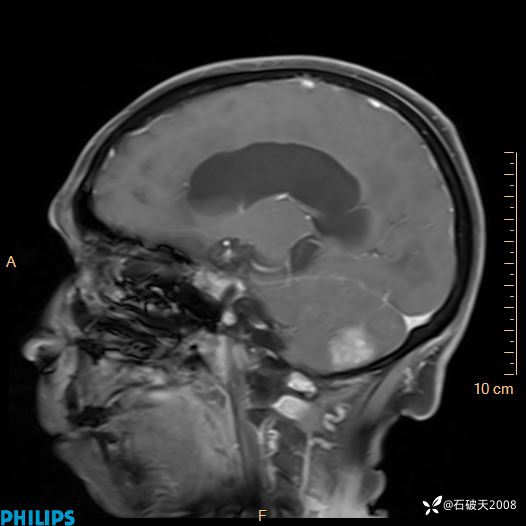

增强矢状位